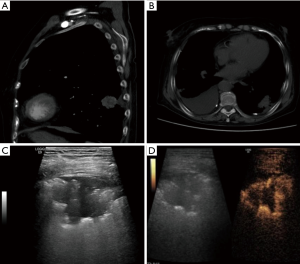

Total of 92 peripheral lung lesions were note with mean diameter of 3.2±1.1 cm (range, 1.2–9.2 cm), including 39 small lesions with a diameter of 1–2 cm and 53 large lesions with a diameter greater than or equal to 2 cm. All 92 lesions had either uniform or inhomogeneous hypoechogenicity on gray-scale ultrasound, 79 lesions were hypovascular and 13 lesions were hypervascular on Doppler imaging. Fifty-two patients were performed percutaneous biopsy by CEUS guidance and 40 patients were performed by traditional ultrasound guidance. Of 52 lesions by CEUS guidance, 27 (51.9%) showed non enhanced necrosis areas on CEUS and only 5 of them showed liquefaction necrosis areas on gray-scale ultrasound, a large narrow base lesion sized 3.5cm for high risk of pneumothorax was ignored on gray-scale ultrasound and discovered by CEUS preprocedure, the other 51 lesions displayed with wide base on gray-scale ultrasound and CEUS (Figures 3,4). Of 40 lesions by traditional ultrasound guidance, 4 showed liquefaction necrosis areas on gray-scale ultrasound.

The most common complication of ultrasound-guided percutaneous biopsy for peripheral lung lesions is pneumothorax, the incidence of pneumothorax is 1–6% (13-15). In the paper, the incidence of pneumothorax in this study was 3.3% and all were mild pneumothorax without thoracic intubation and drainage, which was similar to relevant literature reports by ultrasound guidance and far lower than the incidence of CT pneumothorax at 20.5% (5). Pneumothorax occurs easily in small lesions with a diameter of 1–2 cm, especially those around 1cm in diameter, which is mainly related to the deviation of the guidance, the patient's respiratory movement and the presence of gas reverberation artifacts. Priolal reported that the risk of pneumothorax in lesions smaller than 2cm may be 17-fold higher than in larger lesions (16). In the paper, 3 cases had pneumothorax, 2 cases with small lesion size of 1–2 cm and 1 case with a large lesion size of 3.5cm, the latter patient’s pneumothorax was due to her narrow-based lesion less than 1 cm like a pedicle, it was first ignored on gray-scale ultrasound because of lack of typical features and discovered by CEUS later. In early phase on CEUS, the narrow-based lesion displayed circular high enhancement around it and the wide-based lesion displayed semi-circular high enhancement around it, which was due to retaining normal the pulmonary arteries perfusion in the air-conditioning lung tissue around the lesion. Pneumothorax complication in this case was almost inevitable, fortunately we seized the only opportunity for biopsy and obtained "non-mucinous alveolar carcinoma" confirmed pathological findings depending on one slice of lesion’s tissue sample. So, in ultrasound-guided biopsy for peripheral lung lesions, we should pay attention not only to the size of the lesion but also to the base width of the lesion preprocedure (10,11), CT imaging for lung lesions being more accurate and reliable than US, it is very important for understanding the characteristics of lesions by CT imaging in ultrasound-guided biopsy for peripheral lung lesions. Except for the lesion’s size and the base width, breath control is also very important to prevent pneumothorax, all patients should be trained to hold breath preprocedure. In ultrasound-guided biopsy for peripheral lung lesions, once pneumothorax occurs, the lesion cannot be displayed and biopsied repeatedly, “one shot” biopsy should be prepared for patients with high risks of pneumothorax.

Priolal reported that the diagnostic accuracy rate of lesions >5 cm in size was 78%, and the diagnostic accuracy rate of lesions <5 cm in size was 87%, which was related to the high incidence of liquefaction necrosis (16). CEUS is more sensitive and reliable than traditional ultrasound in identifying focal necrosis of lesions, needle biopsy of peripheral lung lesions under CEUS guidance is receiving increasing attention in recent years (12,22-27). In the study, preprocedure CEUS was performed in 52 lesions in 52 consecutive patients to evaluate non-enhanced focal necrosis and determine the lesions’ sampling part in order to improve histopathologic confirmation rate of puncture biopsy, 27 (51.9%) showed no enhanced focal necrosis, and among them only 5 showed liquefaction necrosis on gray-scale ultrasound. The pathological confirmation rate of puncture biopsy under CEUS guidance was higher than that under traditional ultrasound guidance, but no significant difference was observed, which perhaps due to multiple puncture attempts and small numbers. Beyond above, CEUS can also be used for the preliminary qualitative evaluation of peripheral lung lesions. Previous studies have shown that blood supply to pulmonary malignant tumors originates mainly from the bronchial arteries and manifests as delayed enhancement on CEUS, pneumonia, atelectasis and pulmonary consolidation, on the other hand, exhibit early enhancement due to retained normal blood perfusion (12,22-27), our results conform to that dealt with in the literature. In addition, we also found that tuberculous nodules and inflammatory granulomas chronic inflammatory benign lesions showed delayed enhancement similar to malignant tumors, of whom the similarity of blood perfusion patterns may be an important reason hard to distinguish from one another by various imaging techniques. With image technology progressing faster than ever, biopsy for histopathological examination guided by various images (including ultrasound) is still irreplaceable in lung lesions.